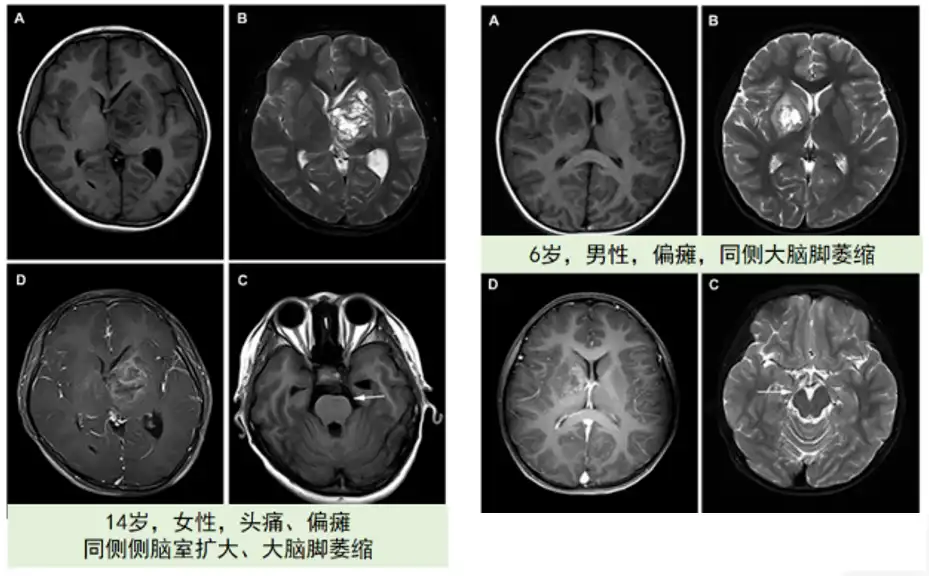

影像学:MRI是核心工具,可清晰显示肿瘤位置与脑室扩大;CT用于评估钙化或脑积水。